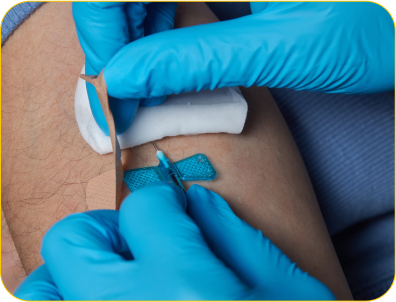

Buscam trabalhar com terapias injetáveis e não ser considerado um médico charlatão.

Querem ter o passo a passo exato para dominar as terapias injetáveis.

Querem ter total segurança para prescrever tratamentos endovenosos e intramusculares.

Precisam saber na prática como utilizar os injetáveis para chegar aos objetivos dos seus pacientes!

Estudos recentes destacam a eficácia das terapias nutricionais injetáveis em diversas condições clínicas:

Reposição de Nutrientes em Pacientes Bariátricos: A Sociedade Brasileira de Cirurgia Bariátrica e Metabólica (SBCBM), em conjunto com a Associação Brasileira de Nutrologia (Abran), discutiu a importância da reposição de nutrientes por vias oral, intramuscular ou endovenosa em pacientes pós-cirurgia bariátrica. A suplementação adequada é essencial para prevenir deficiências nutricionais e complicações associadas.

Impacto no Estresse Oxidativo e Inflamação Crônica: Pesquisas indicam que as terapias nutricionais injetáveis podem reduzir o estresse oxidativo e a inflamação crônica, contribuindo para a melhoria da função mitocondrial e do bem-estar geral dos pacientes.

O QUE VOCÊ VAI APRENDER NA IMERSÃO?

Como adequar a sua clínica para Vigilância Sanitária.

Protocolos para Obesidade, Hipertrofia, Longevidade e Qualidade de Vida.

Como manejar os Efeitos Colaterais das terapias injetáveis.

Quais Terapias Injetáveis não possuem comprovação científica.

Discussão de Casos Clínicos.

Base teórica da Terapia Nutricional Injetável.

Estresse Oxidativo, Inflamação, Sistema REDOX.

Quando fazer EV e quando fazer IM.

Quais medicamentos podem ser associados às terapias injetáveis.